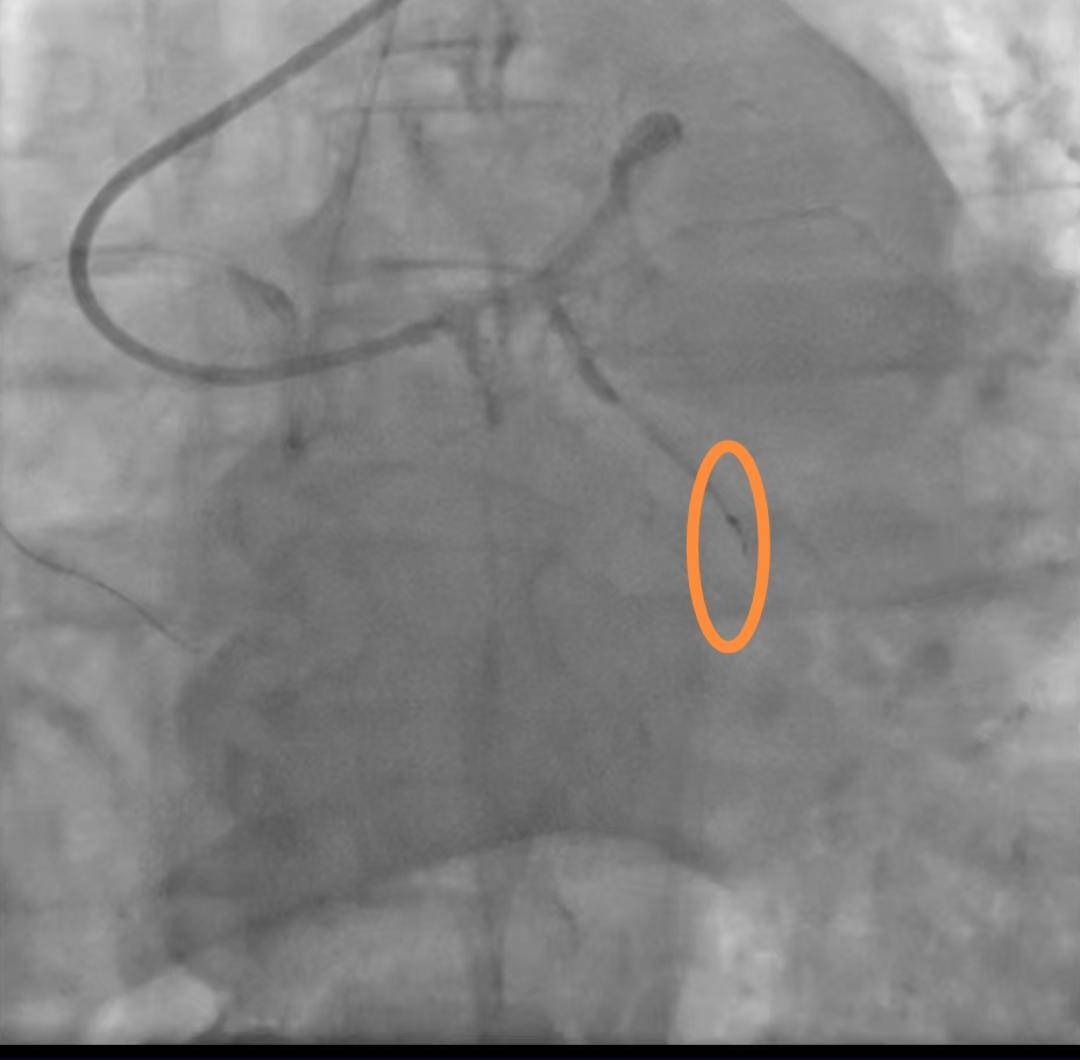

断裂的导丝(受访者供图)

病例资料显示,手术操作过程中出现回撤导丝困难,送入微导管尝试至坎顿处未成功,退出微导管时远段导丝断裂,多途径尝试取出断裂导丝均未能成功。

同日,院方请心血管外科一病区会诊,会诊意见为:回旋支内见离断的介入导丝,外科取出导丝意义不大,建议内科治疗。